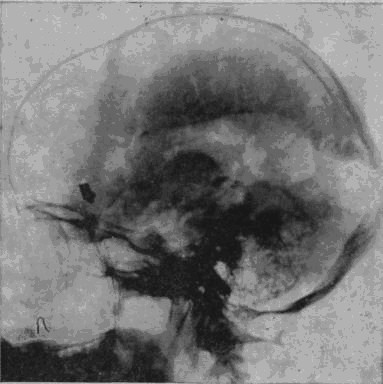

«Младший лейтенант Засецкий, 23 лет, получил 2 марта 1943 года пулевое проникающее ранение черепа левой теменно-затылочной области. Ранение сопровождалось длительной потерей сознания и, несмотря на своевременную обработку раны в условиях полевого госпиталя, осложнилось воспалительным процессом, вызвавшим слипчивый процесс в оболочках мозга и выраженные изменения в окружающих тканях мозгового вещества».

Рис. 1а. Рентгеновский снимок черепа больного Засецкого после введения воздуха в желудочки мозга (пнеймоэнцефалограмма). На нем можно видеть резко расширенный левый боковой желудочек и скопление воздуха в подоболочечных пространствах мозга теменно-затылочной области левого полушария

Осколок внедрился в вещество задних, теменно-затылочных отделов мозга и разрушил мозговую ткань этой области.

Ранение осложнилось воспалительным процессом; он не распространенный, местный, ограничен лишь областями мозга, примыкающими к непосредственному месту ранения, но теменно-затылочные отделы левого полушария, отделы, так тесно связанные с анализом пространственного мира, необратимо повреждены, и уже начинается процесс образования рубцов, который неизбежно повлечет за собою частичную атрофию расположенных вблизи ранения участков мозгового вещества.

Рис. 16. Черное пятно в правом полушарии – осколок, расположенный под кожей от поверхностного шрапнельного ранения, полученного им за год до основного ранения

И через десять лет после ранения – еще одна выписка из истории болезни, на этот раз сделанная на основе рентгенограммы.

В спинномозговой канал введен воздух. Он поднялся вверх, заполнил контуры желудочков мозга и те пустоты, которые образовались в результате сморщивания вещества отделов мозга, непосредственно примыкающих к месту ранения. «Процесс рубцевания вызвал атрофические изменения в левом боковом желудочке. Стенки его подтянуты к поверхности мозга, подоболочечные пространства резко расширены. Значительный местный атрофический процесс».

Ранение вызвало местную атрофию мозгового вещества левой теменно-затылочной области.